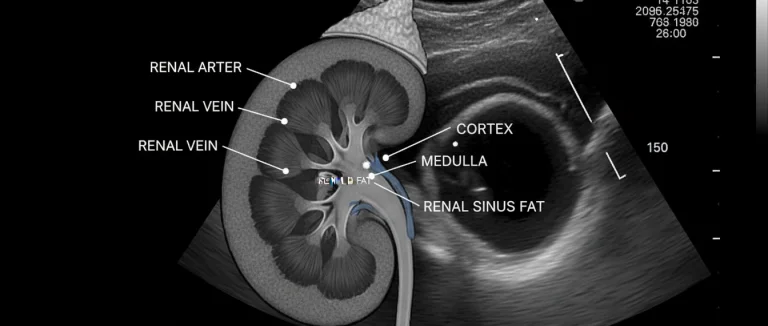

- УЗИ почек и мочевого пузыря – оценивает структуру органов, исключает обструкцию.